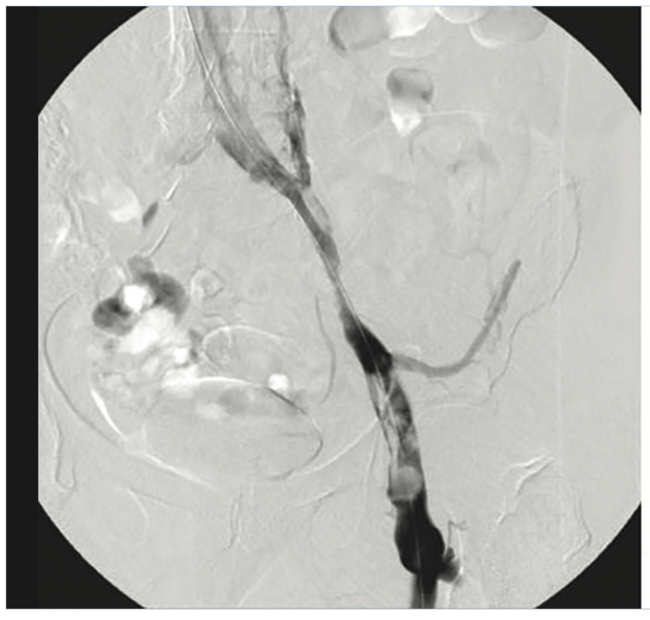

Is there a way to visualize thrombus when you are working in the vessel?

Yes, infusion of the contrast/saline mix is a very helpful trick. Immediately before activating the Aspirex™ Thrombectomy System, you begin this continuous infusion through the sheath landing it at the distal end of the lesion. This allows you to visualize the thrombus burden and see everything you are removing. Whenever you pass through the contrast-filled thrombus with the Aspirex™ Thrombectomy System, you can see what is going into the Aspirex™ Catheter and is being removed. Otherwise, you are doing a blind flight and don’t see anything. Visualization in this way also allows you to work selectively on any remaining thrombus. I would always recommend the infusion of a contrast saline mix, as not only is it valuable for thrombus burden analysis, but also it allows you to see if there is a valve, such as in the femoral veins. When I see a healthy valve, I stop the Aspirex™ Thrombectomy System for those few millimeters or one centimeter, so the valve is not sucked into the catheter. This infusion provides additional safety in my practice.